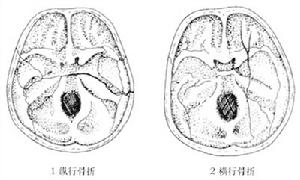

顳骨骨折顱骨骨折多發生於顱底部,1/3的顱底骨折侵入顳骨岩部。依其骨折線分為縱行駛骨折、橫行骨折及岩尖骨折三類。

骨折類型及臨床表現通常以骨折線與岩部長軸的關係,將顳骨骨折分為3種類型:

顳骨骨折2、橫行骨折較少見。約占20%,多由頭顱壓縮性損傷引起。骨折線常起自顱後窩的枕骨大孔,橫過岩錐到顱中窩,有的經過舌下神經孔及岩部的管孔(如頸靜脈孔)、個別的可經內耳道和迷路到破裂孔或棘孔附近,因而骨折線可通過內耳道或骨迷路,還可將鼓室內壁,前庭窗、蝸窗著列,故常有耳蝸、前庭及面神經受孫症狀。如乾音性聾、眩暈、自性眼震、面癱其血鼓室等,面癱的發生率約占50%,且不易恢復。

顳骨骨折(二)橫行骨折:主要由於枕部受到暴力所致。骨折線與岩骨長軸垂直,由顱底後窩橫過岩錐到顱中窩,多從枕骨大孔或頸靜脈窩,橫過內耳道和迷路到顱中窩的破裂孔或棘孔區。內耳損傷重,耳蝸及半規管內常有出血,迷路受損時有較重的眩暈、噁心、嘔吐,檢查可有傾倒及自發性眼球震顫,可持續數周,待對側代償後症狀消失。前庭功能檢查,患側功能喪失,聽力呈感音性耳聾。傷及中耳者較少,偶有迷路損傷同時中耳內壁也被震裂,導致蝸窗膜破裂,鼓室積血,約有半數並發麵癱,且為永久性癱瘓。